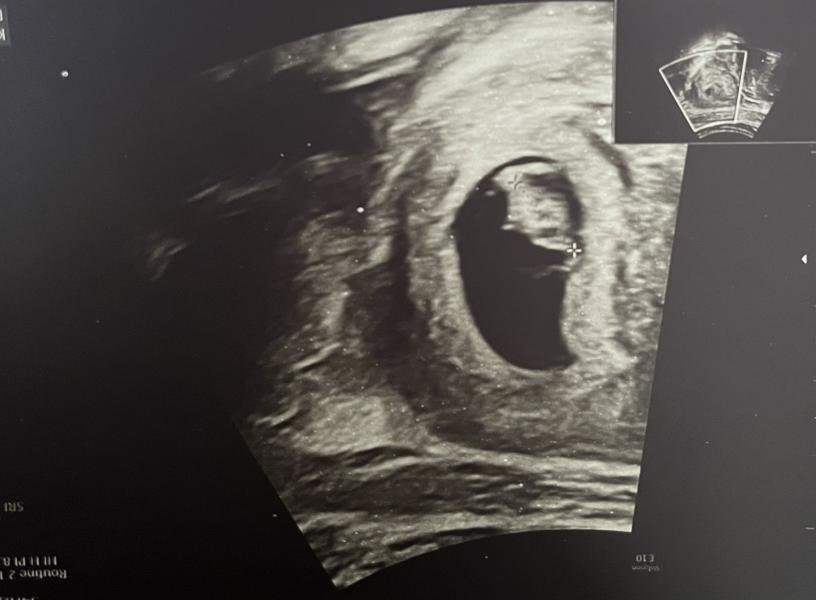

Первое УЗИ: услышала сердцебиение малыша, увидела кролика на снимке, делюсь эмоциями!

Наше самое первое узи, где я услышала сердцебиение малыша 🫶🏻

Случайно перевернула снимок и увидела будто кролик сидит 😂

7,2☺️